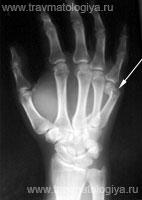

426